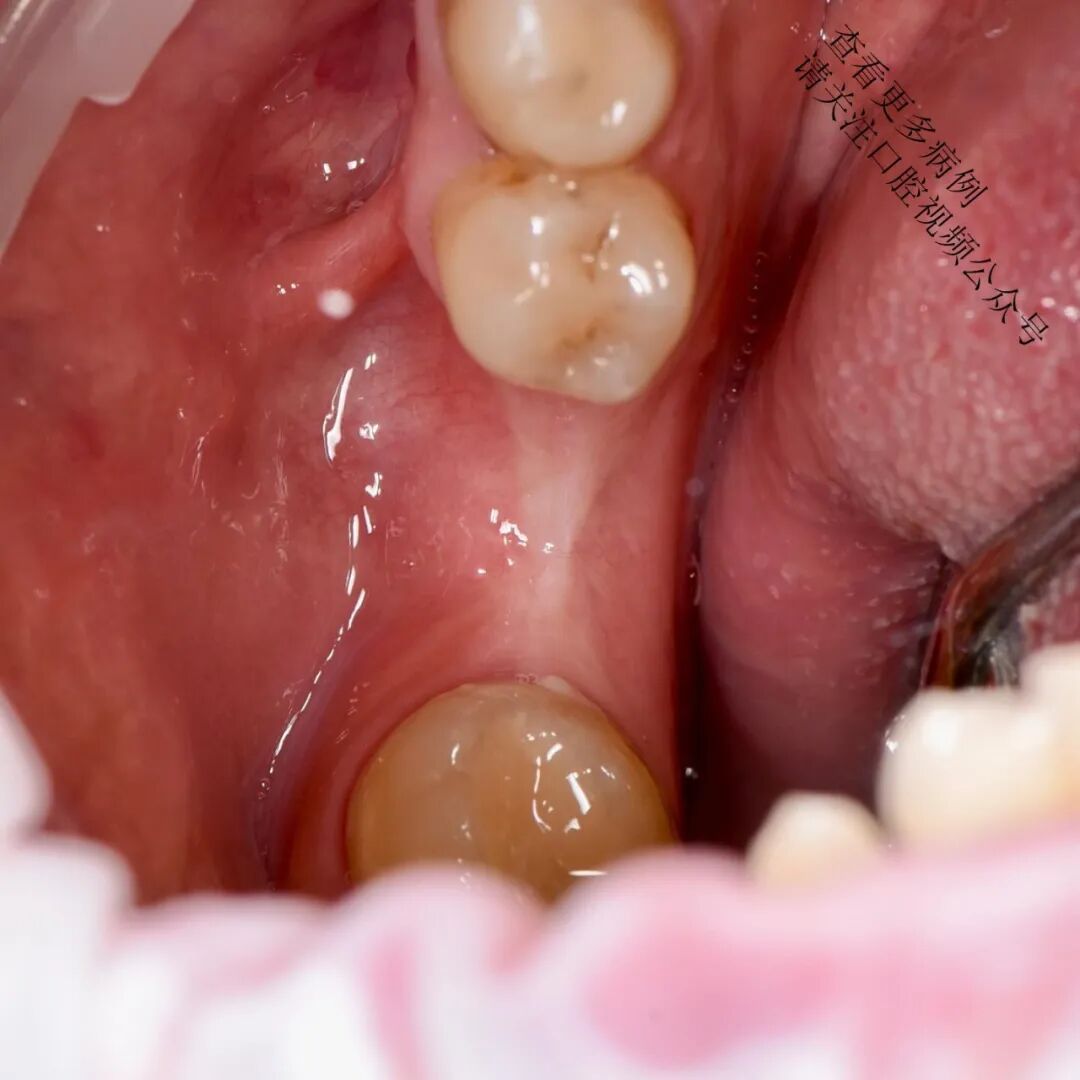

术后4个月复查

临床意义: 此类手术常用于改善种植体周围软组织质量,增强角化龈宽度与厚度,从而提升长期美学和功能稳定性。